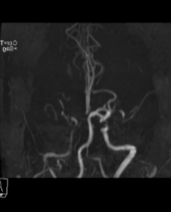

神经介入诊疗中心主任、副主任医师刘俊中接诊后,根据各项检查检验结果迅速判断张女士属于颅内大血管病变。

左侧大脑中动脉和颈内动脉均已闭塞,相当于左侧大脑半球几乎断了供血,手术指征明确。

5 分钟后,张女士被推进介入手术室,急诊脑血管造影进一步确认了血管闭塞情况。